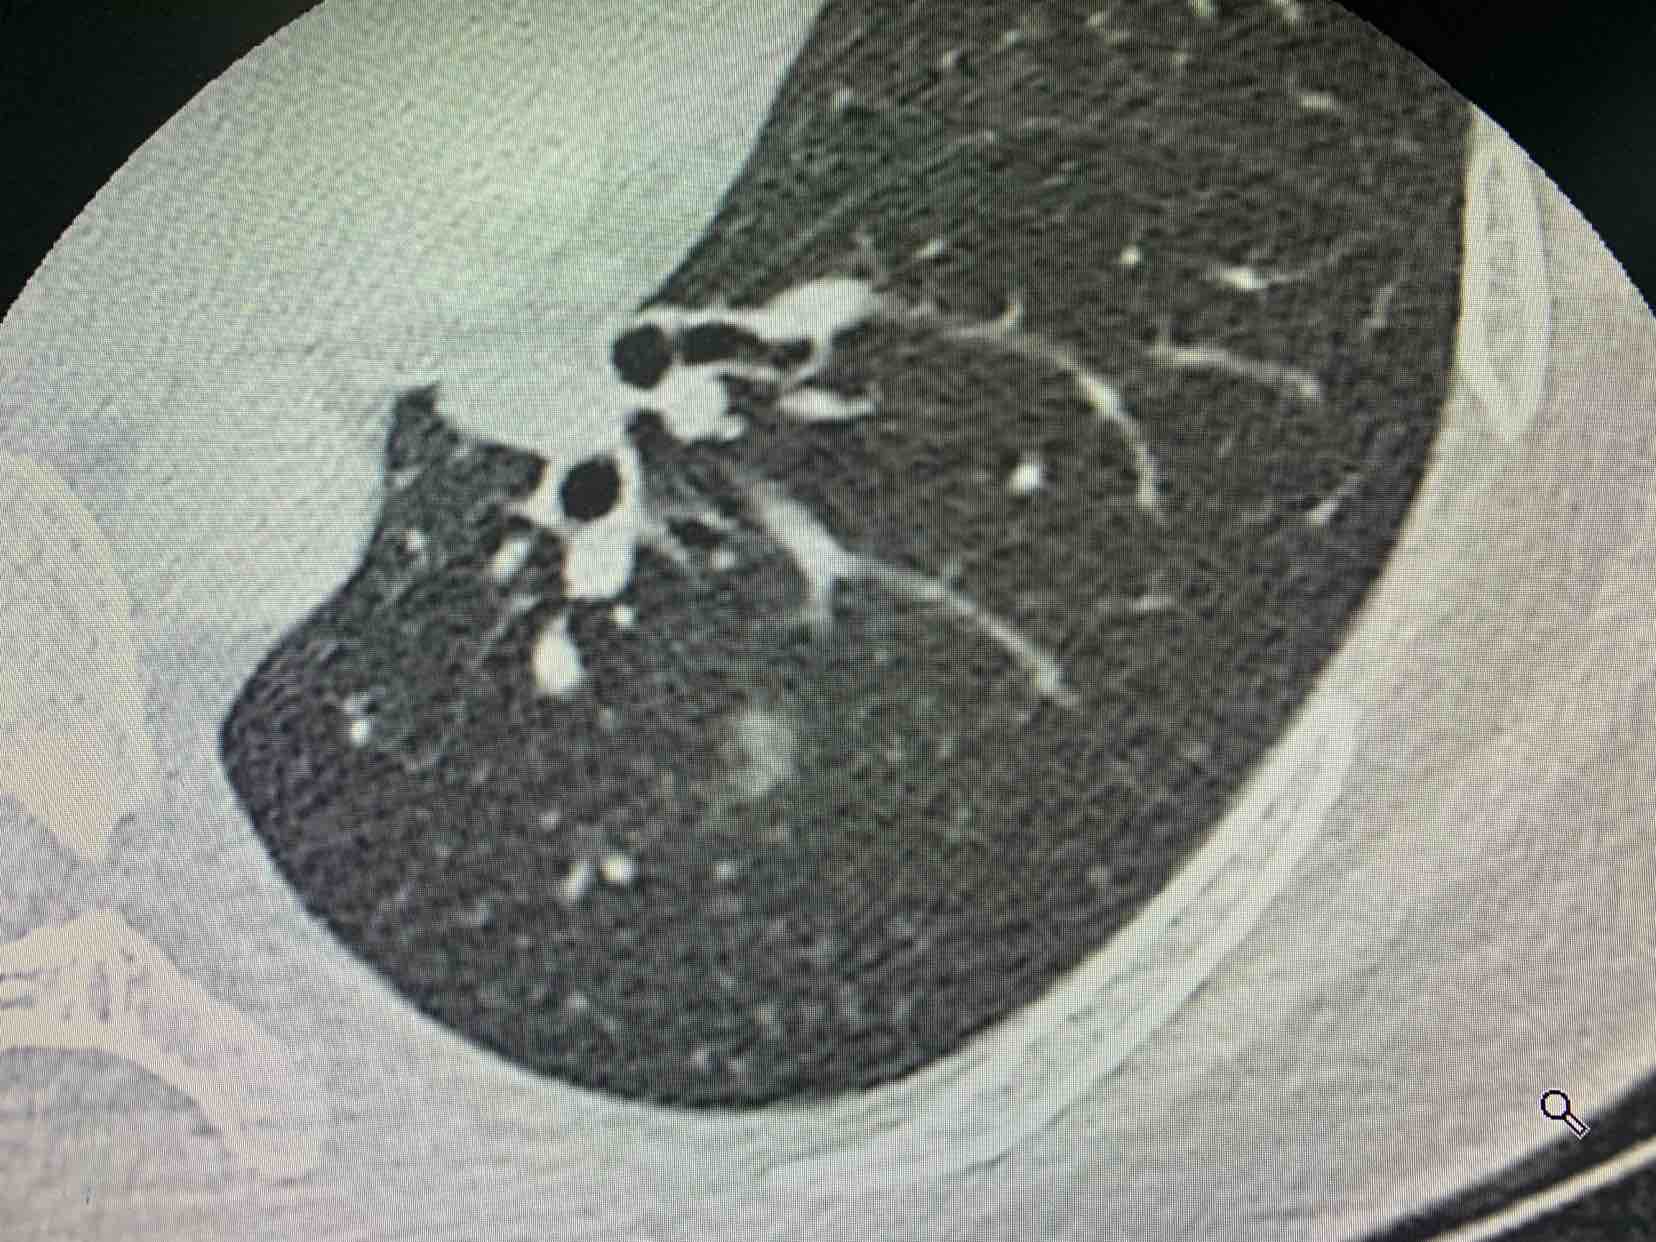

昨天用我自己创新的技术——动脉归属法 做了一台双肺深部结节手术,用一个3厘米的孔洞为患者同时切除了两个早期肺癌病灶,做到真正意义上的微创,根据结节的动脉归属行联合的亚肺段切除,非常成功效果非常好!请相信我们会做得更好,我们也一直奔跑在创新的路上! 展开>